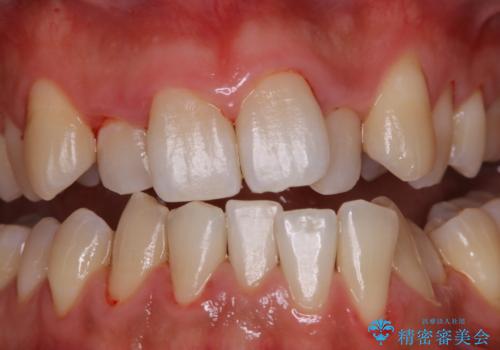

- 忙しく歯科医院でのメンテナンスが1年ぶりとのことで来院されました。PMTC60分コースを行いました。

PMTCを定期的に行い、お口の中を清潔に保つことで長期的に健康なお口の状態でいられることにつながりなす。

毎日かかさず食べる・飲む・噛む・話すなど当たり前の日常生活を快適に送れるように、歯科衛生士による専門的なクリーニングでサポートさせていただきたいと思います。